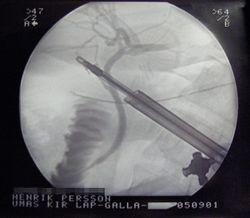

X-ray during Cholecystectomy